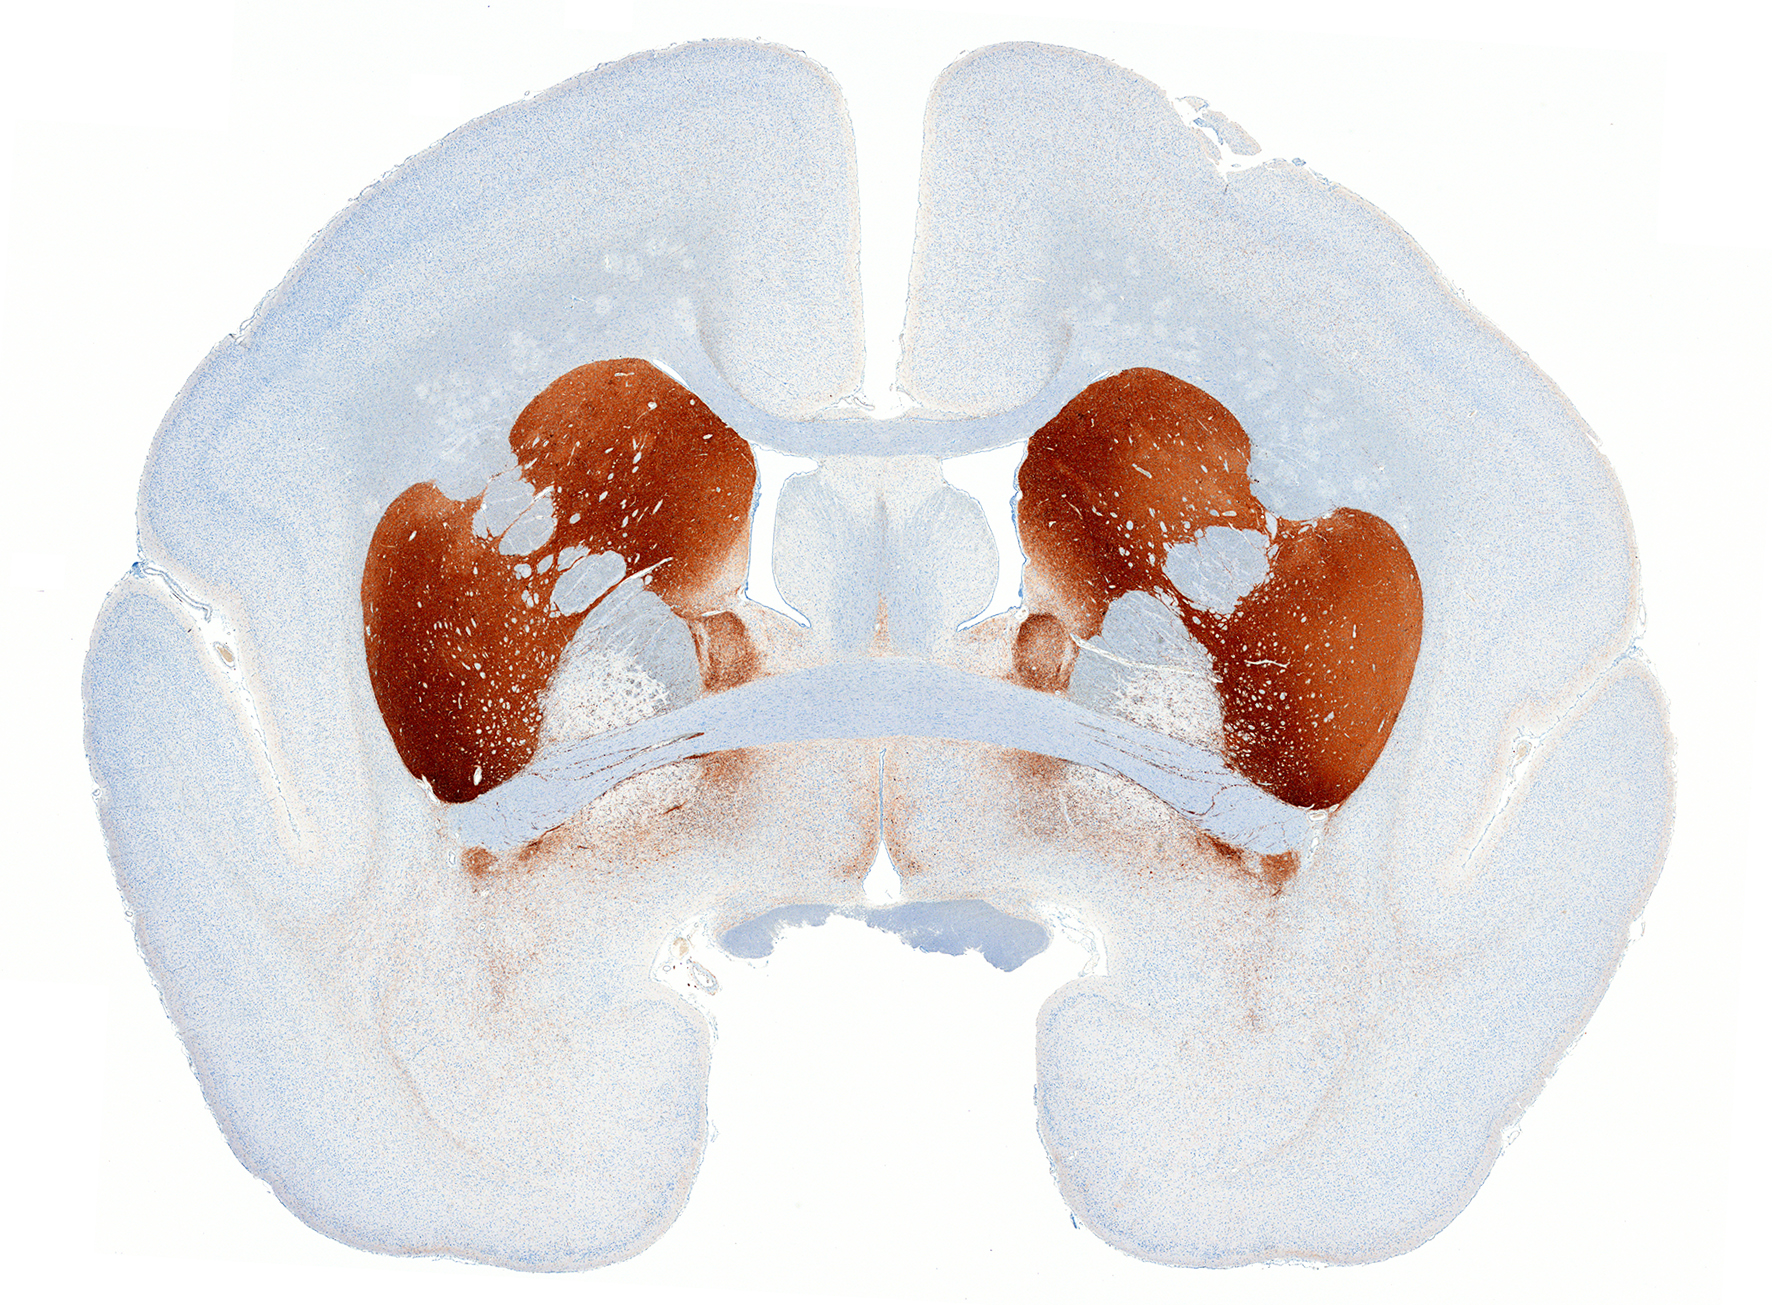

抗TH染色(免疫染色)

(マーモセット脳)